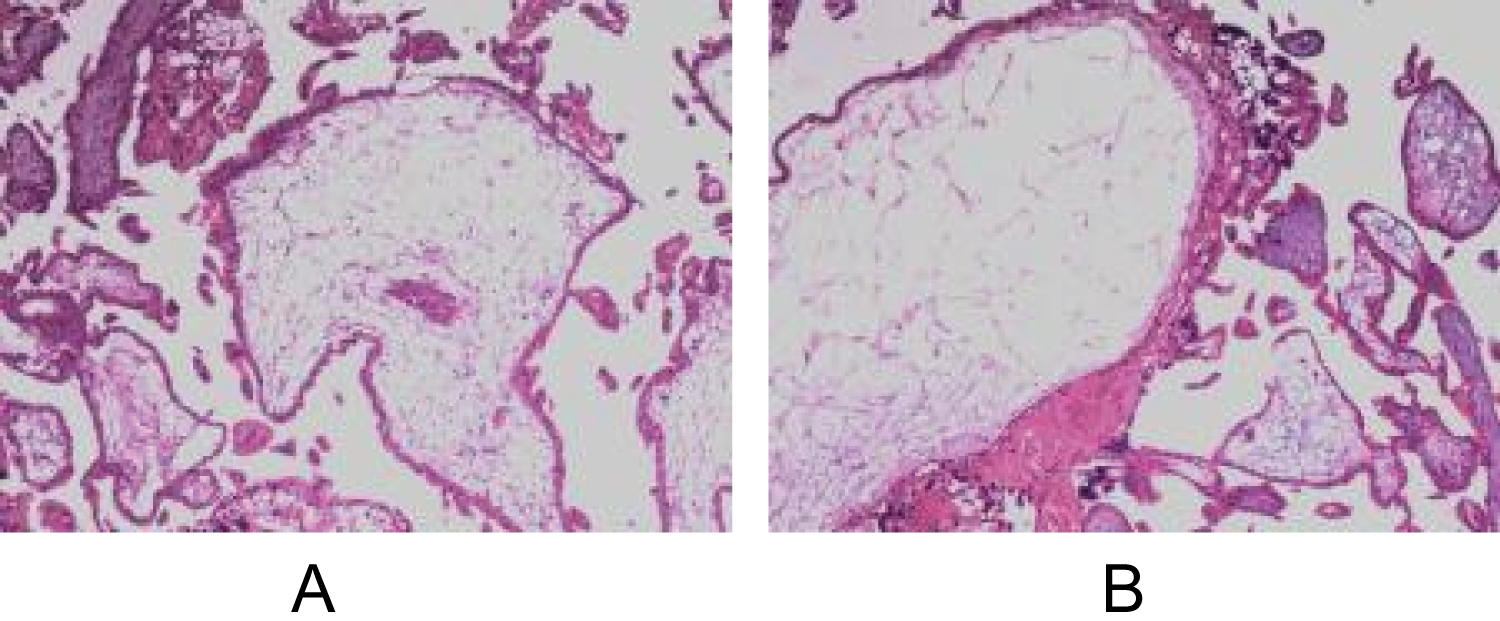

A 33-year-old woman, gravida 4 para 1, presented with vaginal bleeding, slight chest tightness and nausea, underwent a curettage at 5 weeks' gestation for incomplete abortion. While the level of serum β-HCG showed 39576 IU/L on post-surgery day and continued to rise during the following 2 weeks. On the day being transferred to our hospital, the level of serum β-HCG manifested 168208 IU/L, and the transvaginal sonography (TVS) denoted a mass with uneven echo and abundant blood flow in the right lateral wall of uterus, measuring 38 × 43 × 40 mm (Figure 1a and Figure 1b). On the second day of admission, the β-hCG value rose to 216338 IU/L, along with the mass growing to 41 × 44 × 52 mm. However, the chest computed tomography (CT) and craniocerebral CT revealed no abnormalities. Combining with the pathological result of her previous curettage which indicated necrotic villi, decidual tissue and some trophoblast cells, the preliminary diagnosis of GTN and the decision to initiate EMA/CO chemotherapy regimen were made. Two days later, the serum β-HCG ascended to 225000 IU/L, and the ultrasound did not see the reduction of the mass. Due to the unsatisfactory effect, a surgical method was adopted on the tenth day. During the hysteroscopy exploration, a projection surrounded by abundant and tortuous vascular vessels was seen. Rapid pathology manifested the endometrium clamped by forceps did not contain any abnormal composition, leading to the exploratory laparotomy which showed a bulging mass measuring 50 × 50 mm with a purplish-blue-colored surface below the right horn of the uterus (Figure 2a). The chorionic villous tissues bulged out after a fusiform incision was made by a coagulation hook (Figure 2b), then the product of conception was completely removed and the wound was continuously sutured. Intraoperative pathology showed oedematous villi and proliferous trophoblast cells, so the diagnosis of the hydatidiform mole was considered. Given such consequence, adjuvant chemotherapy continued after surgery. One day postoperatively the patient's β-hCG titer dropped to 37955 IU/L and then decreased to 711 IU/L on the tenth day, at which point she was discharged. A follow-up demonstrated the β-hCG level returned to normal. Ultimately, postoperative pathology in combination with immunohistochemistry analysis (P57+) confirmed chorionic villi surrounded by myometrium with no identifiable fallopian tube, validating the diagnosis of intramural ectopic pregnancy (Figure 3a and Figure 3b).

Figure 1: (a) Transvaginal scan showed a mass with uneven echo in the right lateral wall of the uterus; (b) Doppler flow revealed abundant blood flow signals. View Figure 1

Figure 3: (a and b) Histopathological observation showed the characteristic chorionic villi and the smooth muscle tissue was infiltrated with trophoblast cells. View Figure 3